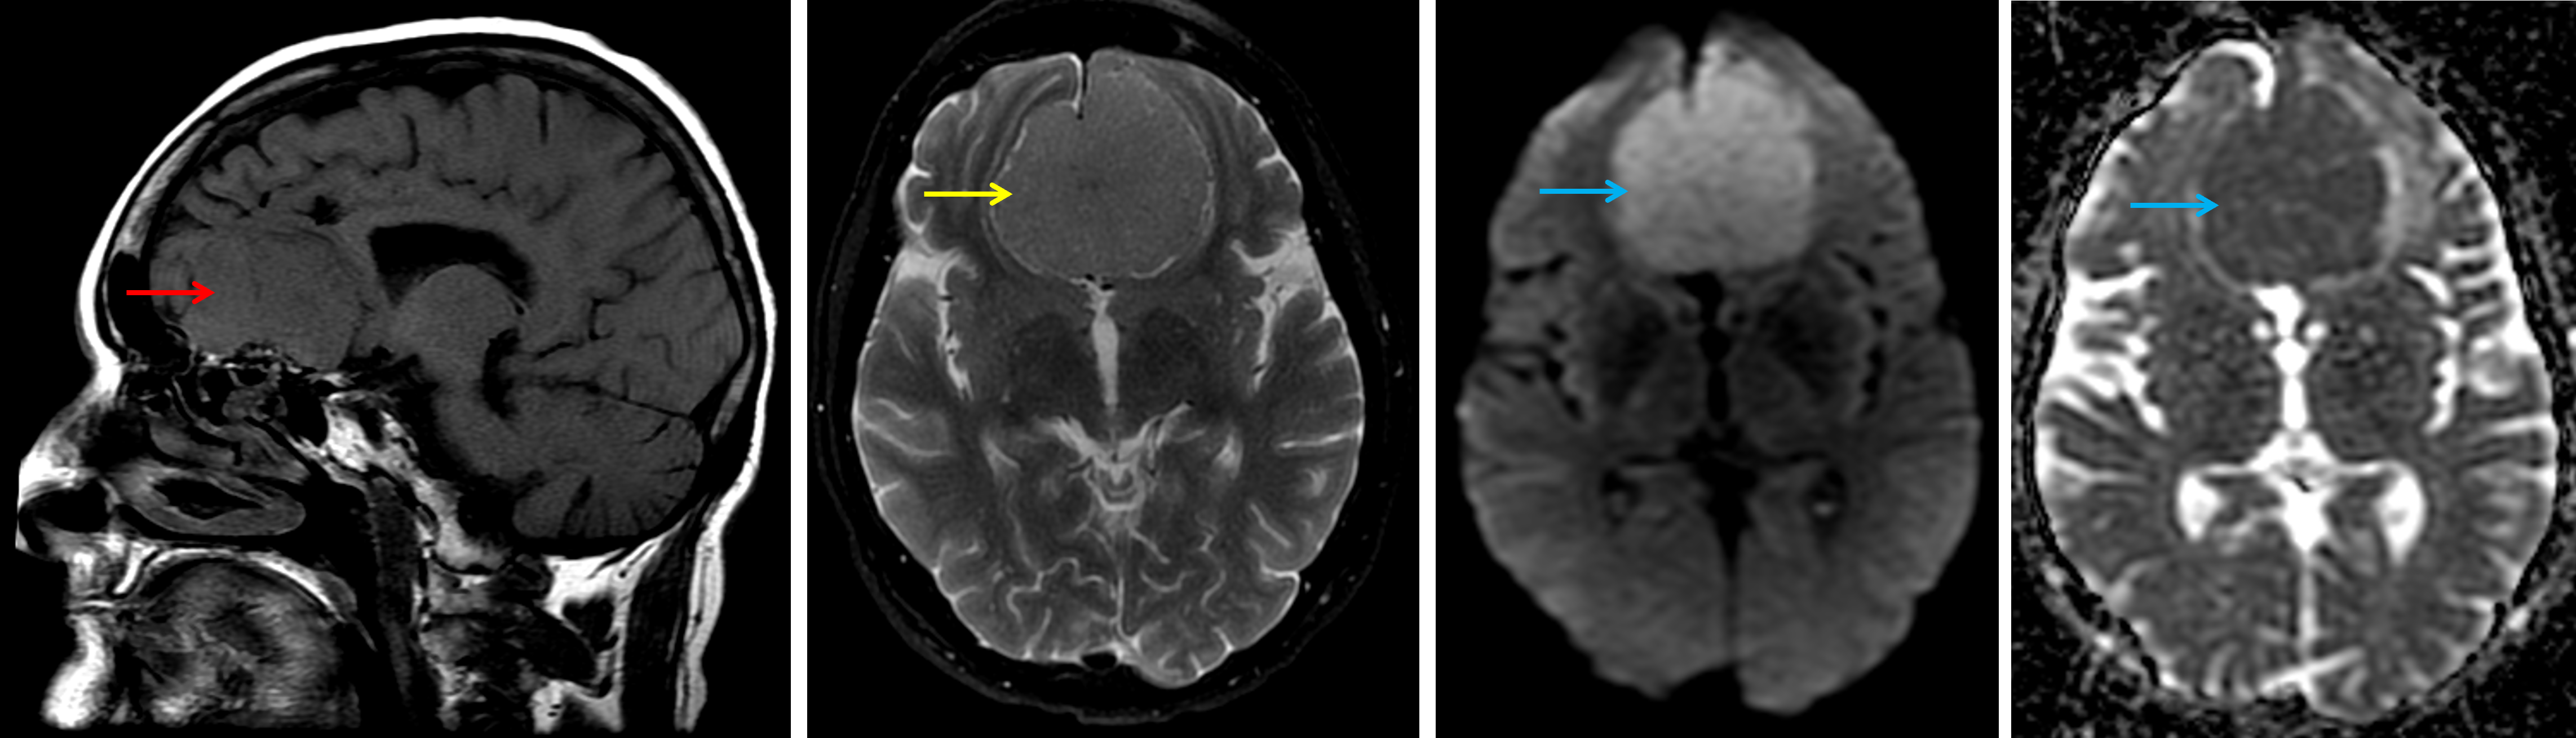

Age: 65

Sex: Female

Indication: Headache

Meningioma